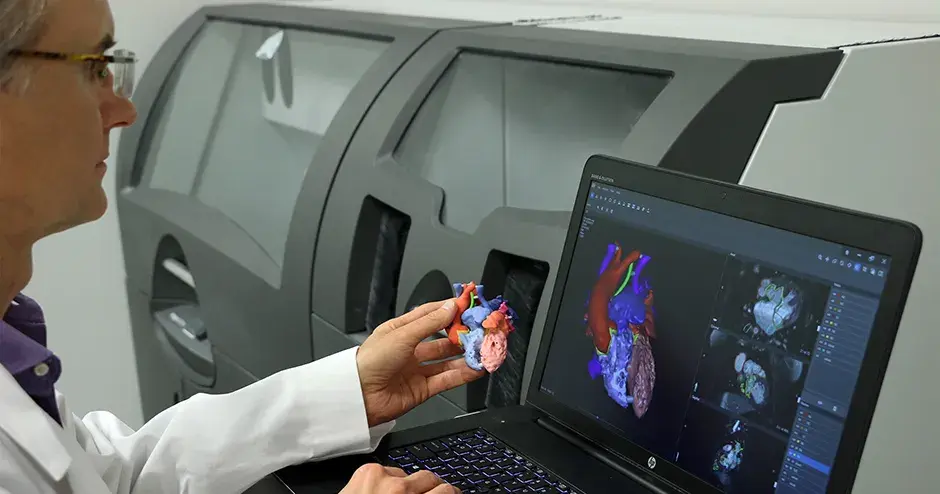

The ability to print patient-specific instruments and devices on demand and on-site is revolutionizing healthcare. By bringing 3D printing and procedural planning technologies to the point-of-care, healthcare providers are improving outcomes1, 2, increasing efficiency4, and lowering the cost of care5. Additionally, hospital operations are discovering that additive manufacturing can help fill supply chain gaps, enabling the production of needed medical supplies on demand.

Craniomaxillofacial, orthopaedics and radiation oncology are just a few of the specialties in which 3D printing at the point-of-care can expedite patient-specific procedures. Applications include:

“As [3D printing] technology becomes more user-friendly for medical professionals, more hospitals will be able to implement end-to-end solutions for personalized surgery. This will disrupt existing healthcare models, improve the quality of care, and crucially, save more lives.”—Gautam Gupta, Ph.D. Vice President and General Manager, Medical Devices, 3D Systems